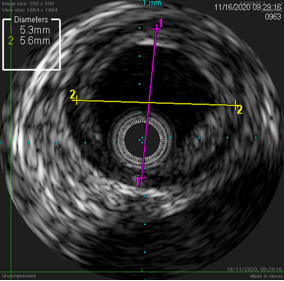

图:近心段(5.3+5.6mm)

图:支架形态规则处,有效面积24.1mm2,最小径 5.3mm,最大径 5.7mm。

图:支架局部不规整,最小径 3.7mm,最大径 5.7mm